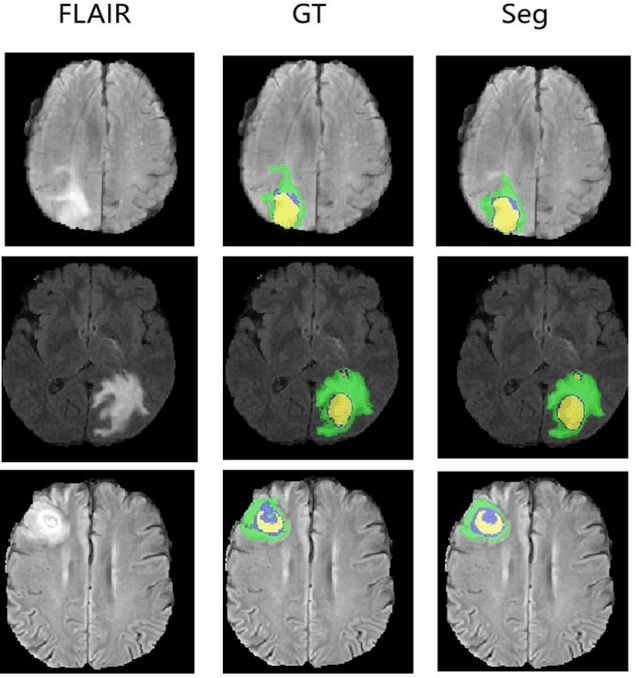

Abstract:Brain tumor segmentation remains a challenge in medical image segmentation tasks. With the application of transformer in various computer vision tasks, transformer blocks show the capability of learning long-distance dependency in global space, which is complementary with CNNs. In this paper, we proposed a novel transformer-based generative adversarial network to automatically segment brain tumors with multi-modalities MRI. Our architecture consists of a generator and a discriminator, which are trained in min-max game progress. The generator is based on a typical "U-shaped" encoder-decoder architecture, whose bottom layer is composed of transformer blocks with resnet. Besides, the generator is trained with deep supervision technology. The discriminator we designed is a CNN-based network with multi-scale $L_{1}$ loss, which is proved to be effective for medical semantic image segmentation. To validate the effectiveness of our method, we conducted experiments on BRATS2015 dataset, achieving comparable or better performance than previous state-of-the-art methods.